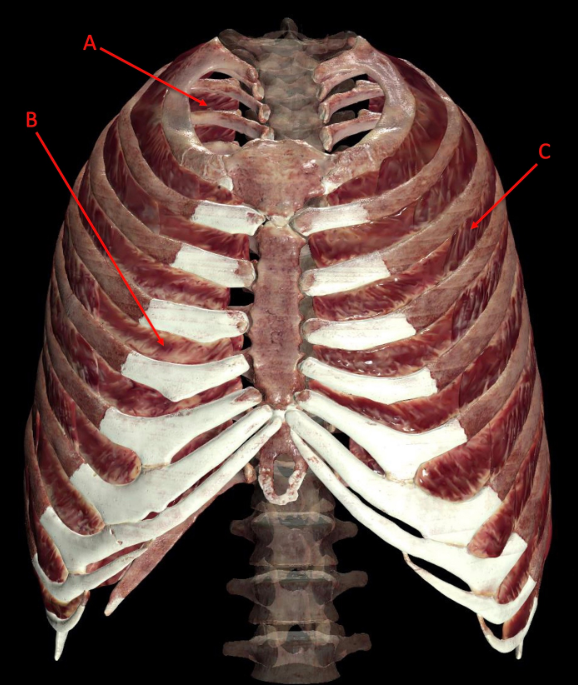

A. innermost intercostal muscle

B.internal intercostal muscle

C. external intercostal muscle